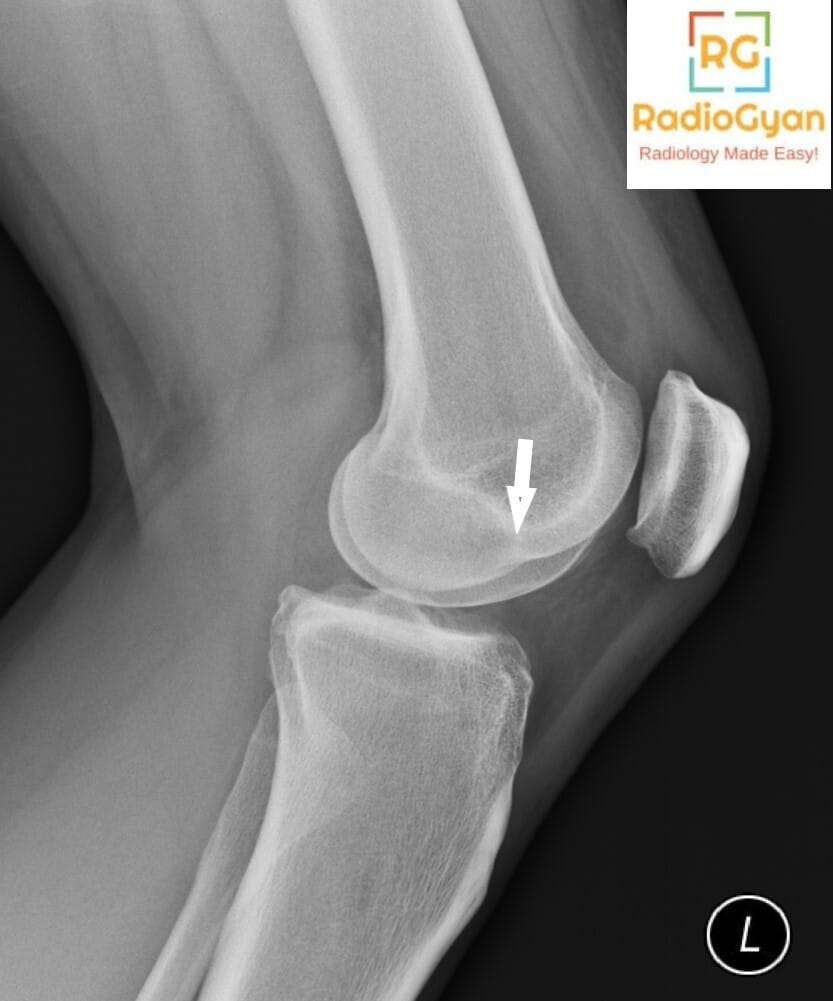

The lateral femoral notch sign is caused by an osteochondral impaction fracture of the lateral femoral condyle typically associated with acute or chronic anterior cruciate ligament (ACL) tears. This sign reflects a bone depression or notch on the lateral femoral condyle resulting from impaction trauma during the injury that causes ACL rupture. It is commonly found in patients with ACL tears and indicates significant bone contusion or fracture of the lateral femoral condyle. Clinically, it is associated with knee instability and ligamentous injury.

It is called the “lateral femoral notch sign” because the abnormal finding is a notch or depression on the lateral femoral condyle seen on lateral knee radiographs or MRI. The term describes the visual appearance of an unusually deep notch in the bone contour of the lateral femoral condyle.

This sign develops because during an ACL tear, the lateral femoral condyle impacts against the lateral tibial plateau forcefully, causing an osteochondral impression fracture. The resulting bone depression increases the depth of the normal lateral condylopatellar sulcus (lateral femoral notch). This bone contusion and impaction fracture deepen the notch beyond physiologic limits, which can be measured on imaging. The lateral femoral notch sign serves as an indirect indicator of the underlying ligamentous injury and knee instability caused by ACL rupture.